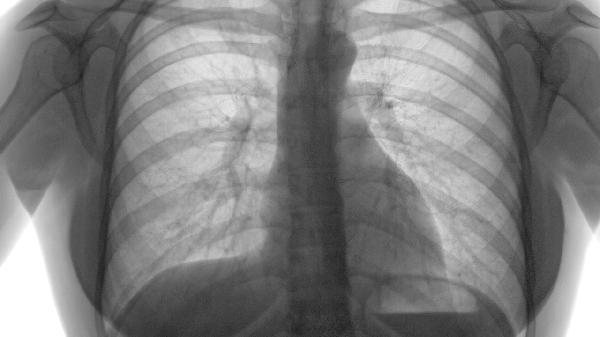

肺上結節多數是在體檢發(fā)現的,那么近年來(lái),隨著(zhù)CT的普及,越來(lái)越多的人在體檢中發(fā)現肺部有結節,如果是在短時(shí)間內出現的結節,并且伴有發(fā)燒,咳嗽呼吸道的癥狀,那么有可能是炎癥,是可以使用抗生素治療的。

雙肺下葉多發(fā)結節

如果結節大于5mm,伴有分葉狀、短毛刺、胸膜牽拉征、胸膜凹陷征等,需要進(jìn)一步給予胸部增強CT以及經(jīng)皮肺穿刺查組織細胞學(xué),進(jìn)一步明確該結節是否已經(jīng)發(fā)生早期癌變。

導致雙肺下葉多發(fā)小結節的原因有很多,主要有以前感染過(guò)肺結核或者肺炎遺留下來(lái)的疤痕,或者是片狀的鈣化點(diǎn)而出現的影像學(xué)征象;肺結節指的是肺內直徑小于或等于3cm的類(lèi)圓形或不規則型病灶。如果結節小于5mm,一般不需要特殊治療,要定期進(jìn)行復查。

還有一部分病人,他肺部有結節,我們要觀(guān)察他以前的這些病灶,如果肺部結節較以前有一個(gè)明顯的變化,明顯的增大或者說(shuō)性狀發(fā)生了改變,在以前的磨玻璃影情況下,出現了實(shí)性的改變,那么這種情況可能是需要去通過(guò)微創(chuàng )手術(shù)手術(shù)切除而達到確診。